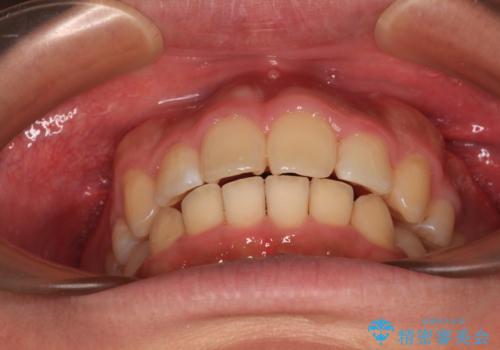

- 学生時代に抜歯矯正した歯列が後戻りしてきたとのことで来院された患者様です。

舌の突出癖が原因で上顎前歯が前方に移動したと考えられたため、舌のトレーニングを徹底して行っていただきながら、後戻りを解消していくこととしました。

マウスピース矯正でもワイヤー矯正でも対応可能でしたが、患者様の希望によりワイヤー装置による矯正治療を行うこととしました。

ワイヤー矯正ということで、上顎大臼歯を後方に移動するための補助装置を併用して、積極的に前歯を引っ込めていくこととしました。

上顎歯列全体がスムーズに後方移動でき、1年で治療を終えることができました。